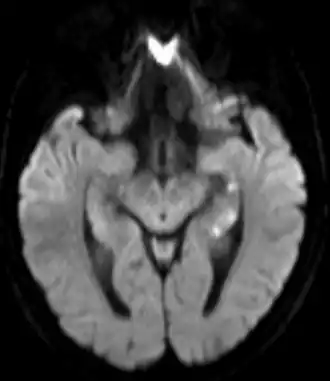

L'examen neurologique est normal pendant et après la crise ainsi que l'imagerie cérébrale[7]. Il peut exister cependant des images punctiformes au niveau de l'hippocampe à l'IRM cérébrale, mais qui sont retardées et transitoires[10], ce qui explique que l'on passe souvent à côté. Le déficit dure, en moyenne, six heures[7].

10. Szabo K, Hoyer C, Caplan LR et al. Diffusion-weighted MRI in transient global amnesia and its diagnostic implications, Neurology, 2020;95:e206-e212